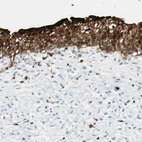

Immunohistochemistry analysis in human urinary bladder and cerebral cortex tissues using HPA004919 antibody. Corresponding HPGD RNA-seq data are presented for the same tissues.